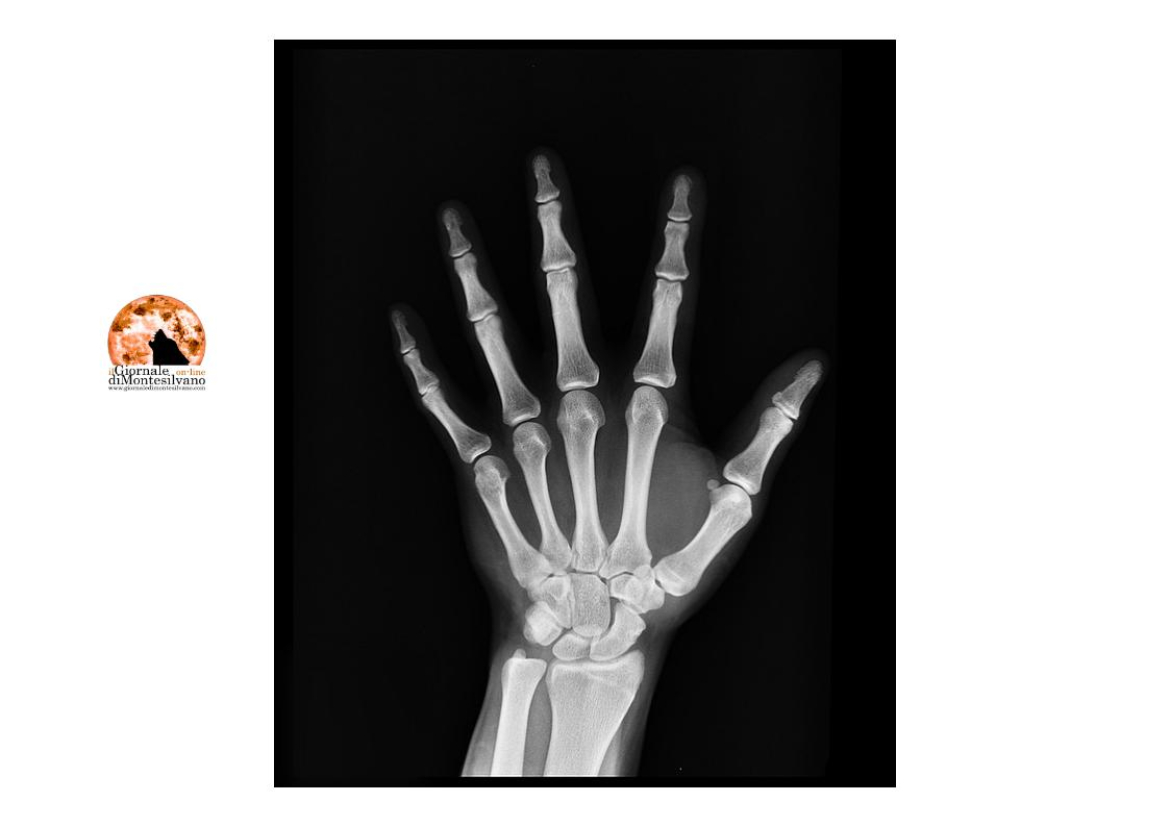

Pescara, 23 lug. - Non solo referti e prescrizioni: a breve i cittadini abruzzesi che utilizzano l’app Abruzzo Sanità OnLine potranno ricevere direttamente sul proprio dispositivo mobile anche le immagini diagnostiche, comodamente a casa propria e senza inutili spostamenti o perdite di tempo.

“Negli ultimi cinque anni – puntualizza Riccardo Urbani, consulente tecnico del presidente Marsilio - la Regione Abruzzo ha fatto enormi passi avanti in ambito digitale e tecnologico. I nostri progetti innovativi hanno consentito ai cittadini di vivere una vera rivoluzione digitale: oggi è possibile prenotare prestazioni sanitarie direttamente dal proprio telefonino, ricevere immediatamente i referti e, a breve, anche le immagini diagnostiche. Grazie al nuovo progetto VNA (Vendor Neutral Archive), inoltre, l'Abruzzo è la prima regione in Italia che consente ai cittadini, da qualsiasi sito sanitario, di accedere ai propri referti e immagini diagnostiche in modo semplice e veloce. E’ inoltre appena partito anche il progetto di telemedicina che aiuterà moltissimo i pazienti con difficoltà di spostamento, facilitando sia l'accesso alle prestazioni sanitarie, sia la riduzione delle liste di attesa”.